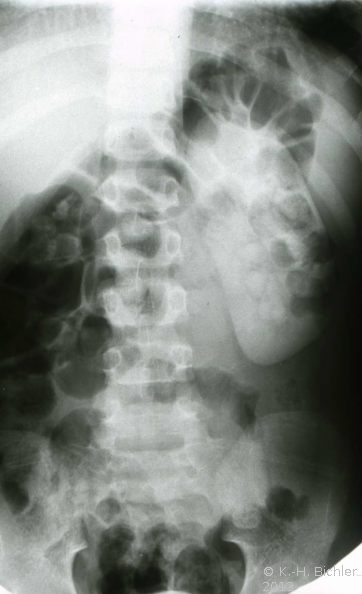

Bei dem 8-jährigen Jungen waren Schmerzen im linken Oberbauch sowie rezidivierende Harnwegsinfekte Ursachen für die Abklärung. sonographisch und röntgenologisch fanden sich Nierenkelchkonkremente in einer Harnstaaungsniere (Abbildungen 21,22,23). Bei der retrograden Sondierung ergab sich ein deutlicher Widerstand in Höhe des Ureterabgangs. Die Freilegung zeigte eine aberrierende Arterie als Abflusshindernis. Nach Durchtrennung des Harnleiters Eröffnung des Nierenbeckens zur Steinentfernung und Abgangsplastik des vorgelagerten Harnleiters. Normalisierung der Abflussverhältnisse.